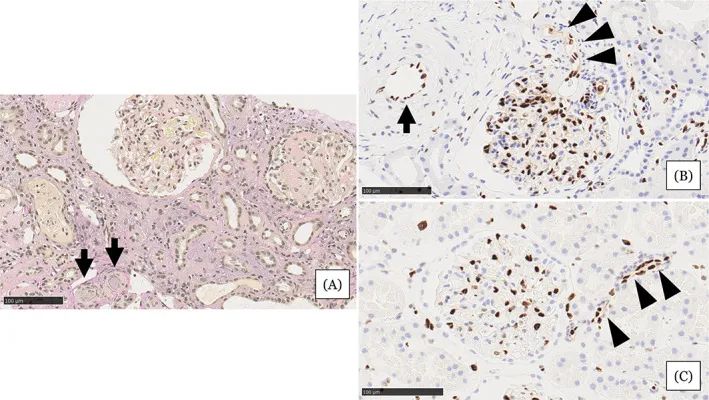

圖注:在住院第31天進(jìn)行的腎活檢結(jié)果。A,顯示小動(dòng)脈被粘液性內(nèi)膜增厚(箭頭)堵塞,腎小球萎縮,毛細(xì)血管壁起皺,嚴(yán)重的間質(zhì)單核細(xì)胞浸潤(rùn)伴腎小管損傷。B,EC細(xì)胞核的缺乏在小動(dòng)脈(箭頭)中很突出。在相鄰的小動(dòng)脈(箭頭)中注意到不同大小的不規(guī)則細(xì)胞核。C,EC的等距核在血壓正常的腎臟供體的腎臟小動(dòng)脈中形成有序的線。比例尺 =100μm